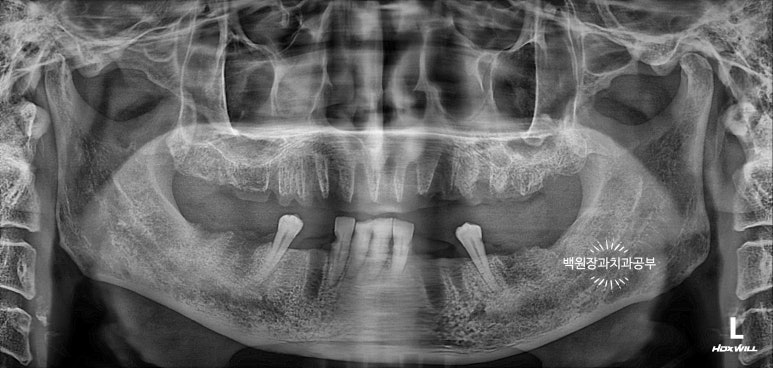

초진 치과 파노라마 사진

저희 환자분께서 처음 내원하셨을 당시 치과 파노라마 사진입니다.

성인의 치아 개수가 총 몇개인지 아시나요? 위턱 14개 아래턱 14개 총 28개입니다.

방문하셨을 당시 위턱은 전체 치아가 발치된 상태였고, 아래턱은 총 6개의 치아만 남아있었습니다.

남아있는 치아들도 치아의 옆면 (=인접면)에 충치가 있는 것으로 보아, 이를 뽑기 전에도 다수의 충치가 있으셨겠구나.. 라는 것을 짐작할 수 있었어요.